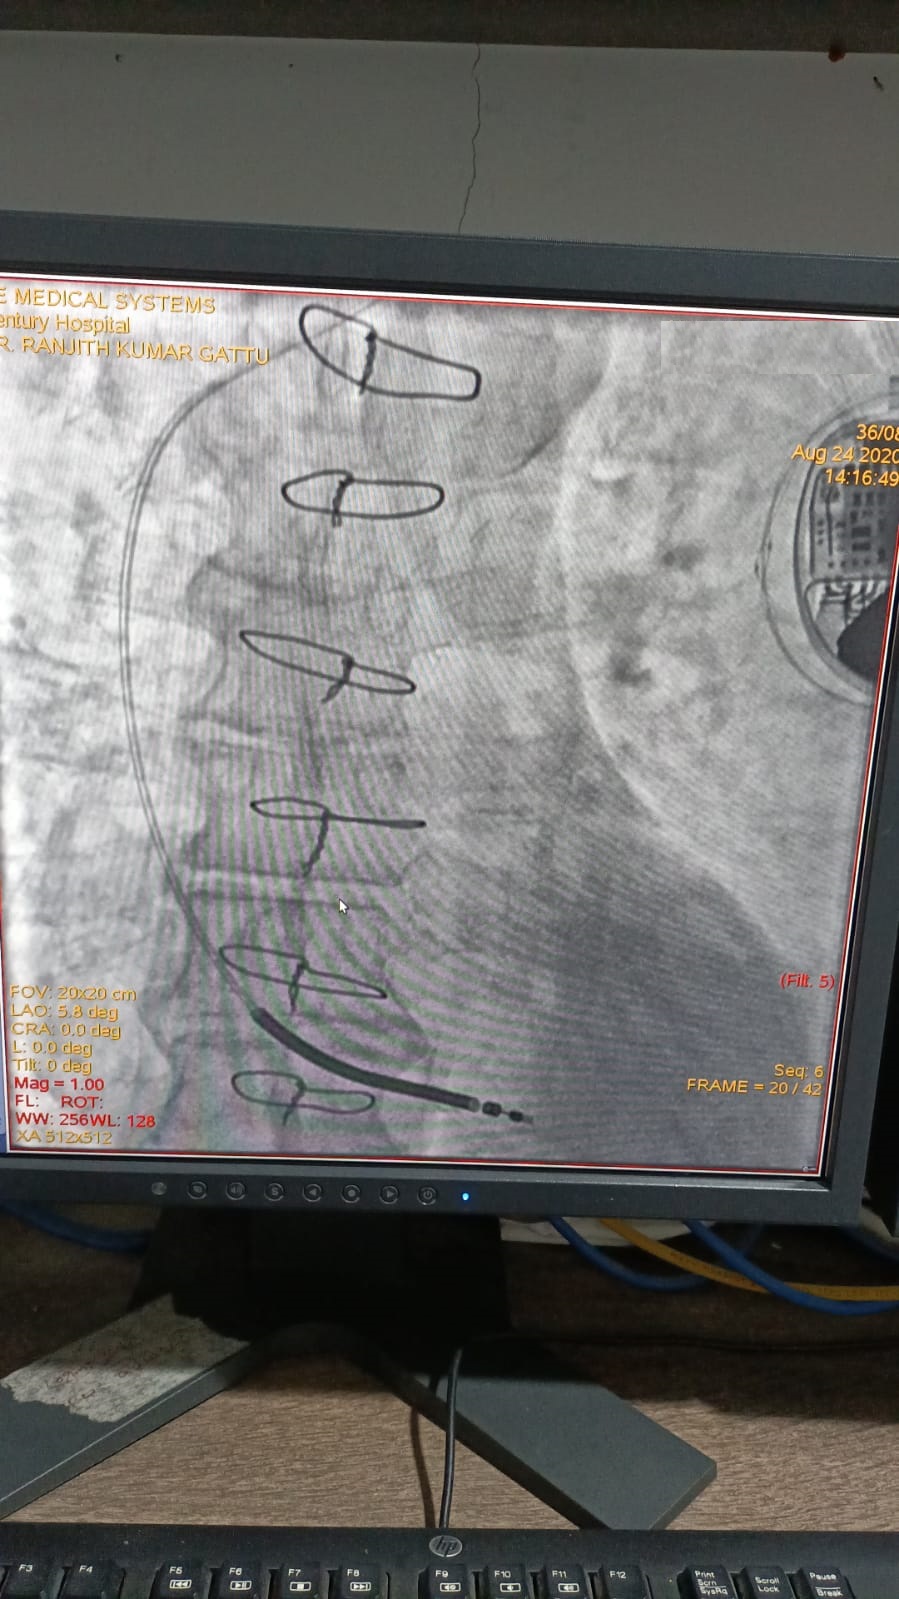

Catheter ablation of arrhythmias